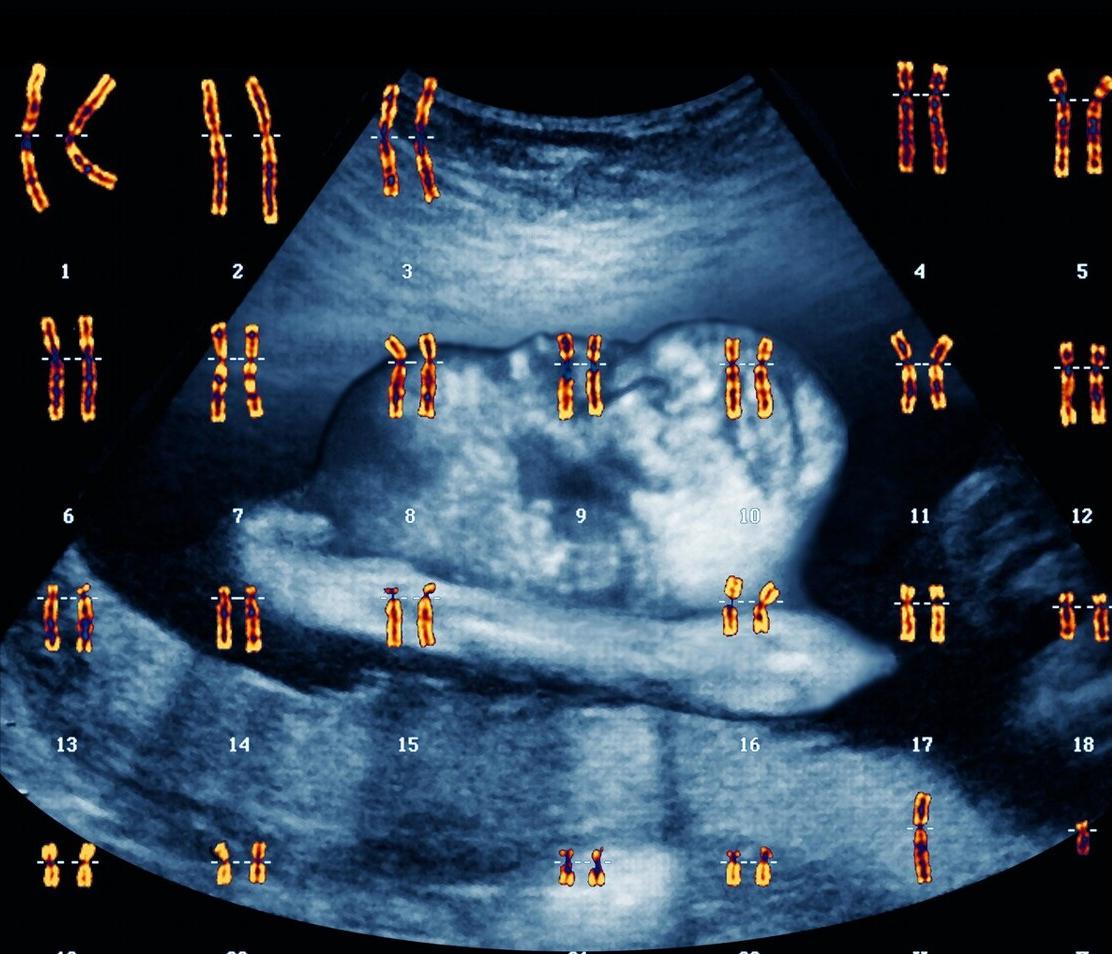

很多人都会以为胚胎染色体异常都是夫妻染色体异常所导致,实际上这是一个误区。胎儿染色体异常概率,只有大概1/5是源于遗传性的,而4/5都是因为精子卵子在结合的过程中,染色体的拆分重组出现错误而导致的。 染色体异常会出现很多典型的状况,比如囊胚培养不成功、移植不着床、流产胎停等等。而第三代试管PGS技术就可以解决这个问题,移植胚胎前进行基因筛查,优生优育。

19年9月胚胎16三体(浙江省某医院只查胚胎核型,同时在那个医院查了夫妻的染色体核型正常),2020年3月胚胎核型正常,但由于各种原因没保下来,2020年10月x性染色体单体,是收费4800的那种,检查资料已上传,拜托您帮我看下我们这种情况我们夫妻需要进一步检查染色体基因吗?是不是一定要做三代试管

答:您曾经2次胚胎染色体异常,分别是16三体和x染色体单体,夫妇染色体正常,都是生殖细胞染色体突变造成的,这是概率性问题,一般考虑再发的概率不高,夫妇染色体不需要进一步检查,已经明确了。如果能自然怀孕,一般不考虑三代试管婴儿。

如果夫妻双方或一方染色体异常,或夫妻染色体正常、女方年龄≥38岁、或有不明原因≥2次的自然流产,或≥2次的胚胎染色体异常,可以考虑胚胎移植前诊断技术助孕,但均需要接受专业遗传咨询后,再决定是否选择胚胎移植前诊断技术。